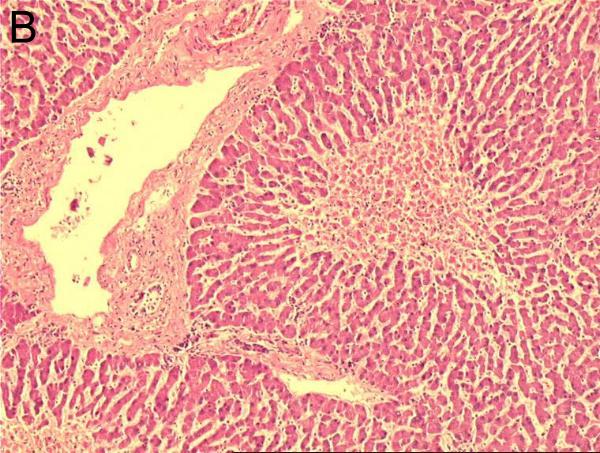

Histologie: Organdiagnose: Die normale Architektur der Leber mit

Leberzellbalken, Portalfeldern und Zentralvenen ist prinzipiell erhalten (A).

Pathologie: In den zentralen Abschnitten der Leberläppchen um die Zentralvenen

zeigt sich eine Leberzellnekrose mit Verlust der Kernfärbung, darüber hinaus

eine starke Blutfülle mit Erweiterung der Sinusoide, die strotzend mit Erythrozyten

gefüllt sind (G,F). Um die Portalfelder herum, die normale Gefäßanschnitte

und Gallengänge zeigen, findet sich meistens ein Saum erhaltener Hepatozyten

(A-F). Differentialdiagnose: Bei der Amyloidose der Leber zeigt sich